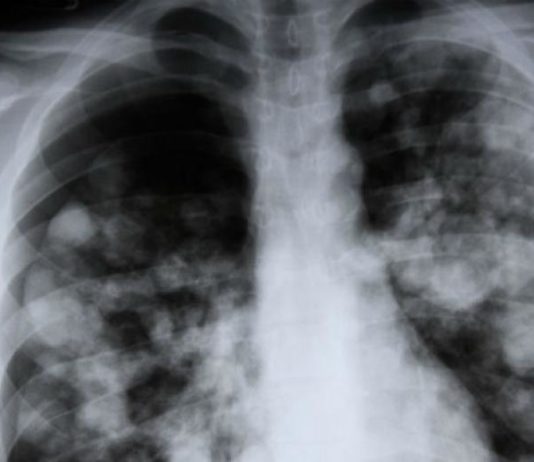

Necesitaba un trasplante doble de pulmón. Lo consiguió, pero al poco tiempo de la intervención desarrolló un cáncer. Los pulmones que había recibido esta paciente francesa eran de una fumadora.

Según un estudio publicado en la revista especializada Lung Cancer, que alerta sobre el riesgo de trasplante de tales órganos,...